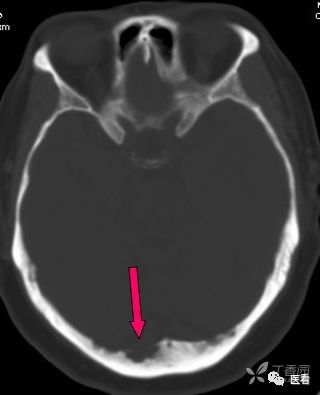

亨氏暗区

颅底(致密)骨产生的横行或放射状伪影,与设备性能也有关系

下图为16拍MSCT,伪影较轻。

此图为双排螺旋 CT图像, 伪影较16层及以上MSCT显著的多。